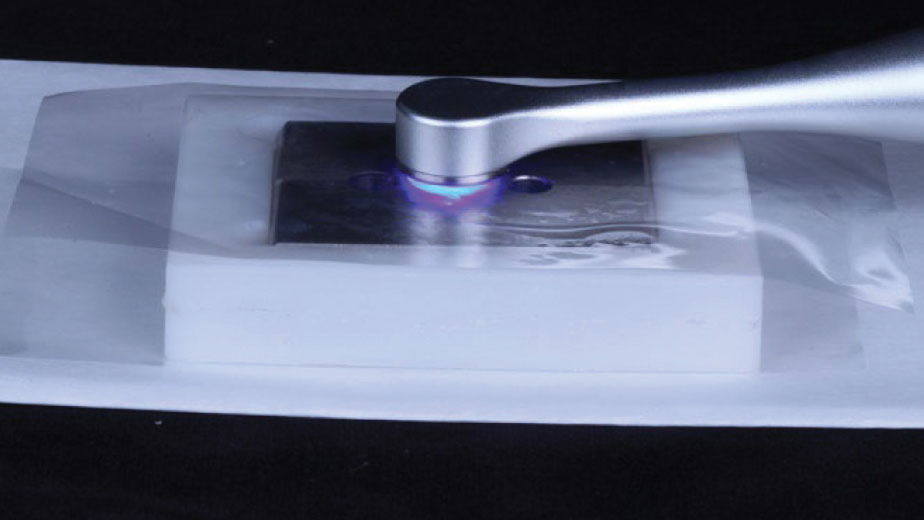

The loss of a tooth can be a stressful event for any individual. Upon learning that a tooth in the esthetic zone has been lost, or is going to be extracted, a patient’s immediate statement is almost always: “I don’t want to lose a tooth!” followed by the question: If that’s going to happen, how do … Read more